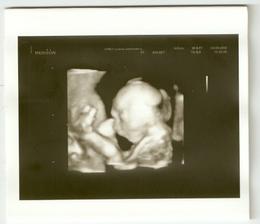

3. září - 4D Utz za námi (Sam váží 484g), byl to neskutečný zážitek se na chvíli podívat za Samem do jeho světa, musím na to pořád koukat (dostali jsme i DVD záznam). Je to nádherný chlapeček (znovu potvrzen), trošku stydlín, ale máš být po kom, že Samíku? 😉 Má krásnou tvářičku, ručičky, prstíky, nožky, ouška.., nosánek bude spíše po mámě, jsem moc pyšná! Už se ho nemůžu dočkat...